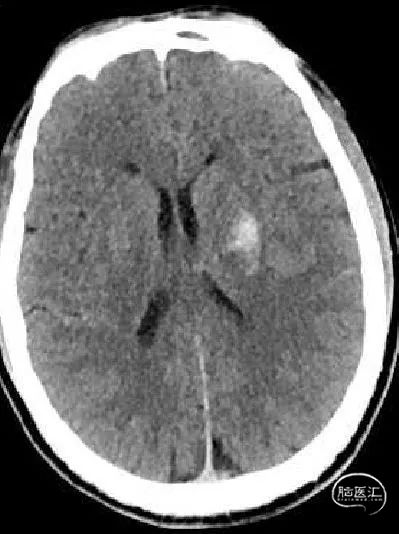

术后2小时复查头颅双能CT:

取栓术后,见少量造影剂渗出。

术后1天复查头颅CT: